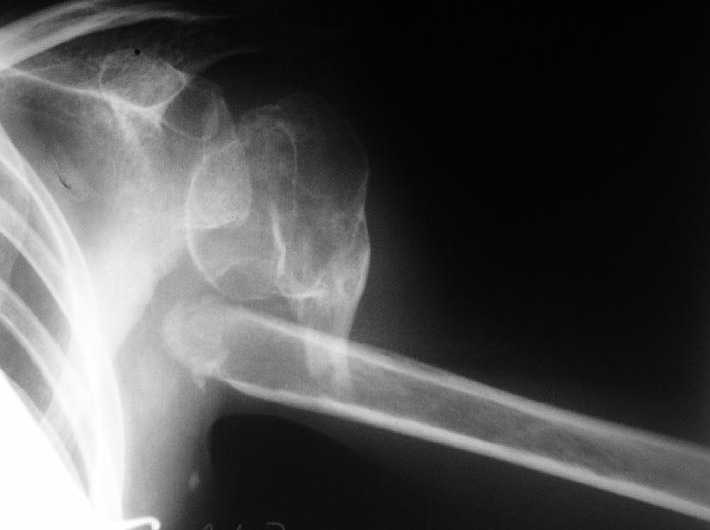

[Ortho] Несращение плеча, деформация головки

Больная 40 лет, множественная травма в июне 2007 года. Лечилась в городской больнице.

Повреждение проксимального отдела плеча вели  консервативно в гипсовой

повязке. В настоящее время больную беспокоят боли в области плечевого

сустава, слабость верхней конечности. Амплитуда движений в плечевом

суставе в пределах 30-40 градусов. Пациентка хотела бы увеличить объем

движений и силу.

Движения сейчас в основном за счет ложного сустава. Варианты -

остеосинтез, артролиз, эндопротезирование, оставить как есть. Как-то

ни один однозначно не привлекает.